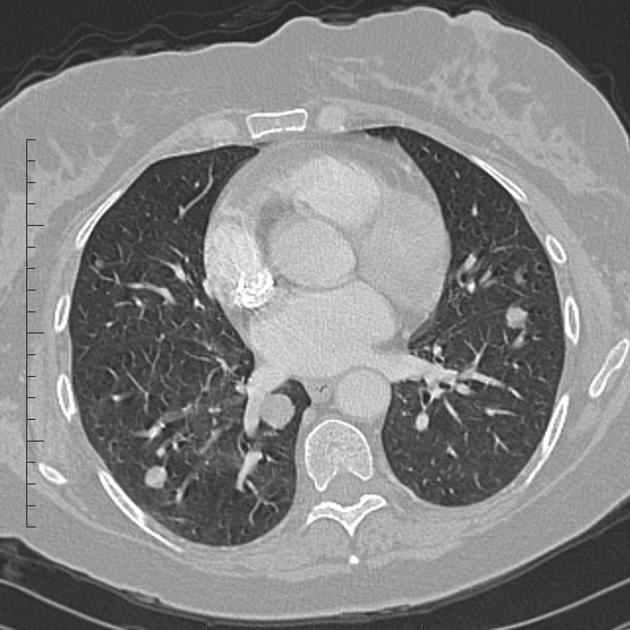

- 흉부 CT: 폐 전이를 가장 정확하게 확인할 수 있는 검사

- PET-CT: 대사활동이 높은 암세포를 찾아내 전신 전이 여부 확인 가능